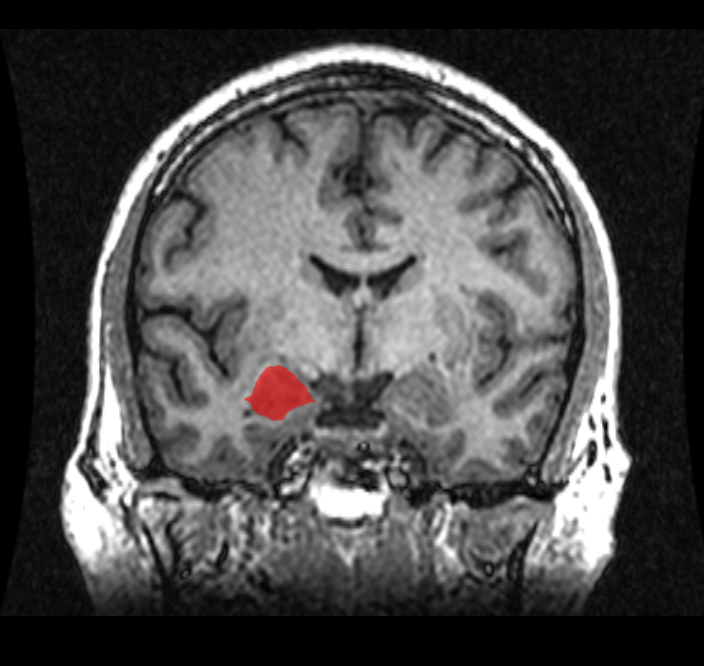

편도체는 뇌의 측두엽에 위치한 아몬드 모양의 구조로, 12개 이상의 신경핵을 포함하며 다양한 뇌 영역과 연결되어 있다. 해부학적으로는 외측핵, 중심핵, 내측핵 등으로 나뉘며, 기저핵의 일부로 간주되기도 한다. 편도체는 정서 처리, 특히 공포와 같은 부정적인 감정을 처리하고, 공포 기억 형성에 중요한 역할을 한다. 또한 정서 학습, 기억 조절, 사회적 행동, 공격성 등 다양한 기능과 관련이 있으며, 불안 장애, 우울증, 자폐증 등 정신 질환과의 연관성도 연구되고 있다. 최근 연구에서는 성적 지향과 편도체의 구조적 차이 간의 상관관계가 제시되기도 한다.

편도체는 해부학적으로 구별되는 여러 핵[6]들의 집합체로, 12개가 넘는 핵이 확인되었다.[7] 이들 핵은 각각 고유한 세부 구조와 뇌의 다른 부분과의 구별되는 연결망을 가지고 있다.[7] 주요 핵 그룹으로는 측측 복합체, 중심핵, 피질핵, 내측핵, 그리고 중간세포 집합체 등이 있다.[4][102]

편도체는 여러 개의 핵[6]으로 구성된 복합체이며, 12개가 넘는 핵이 확인되었다.[7] 각 핵은 고유한 세부 구조를 가지며 뇌의 다른 부분과 구별되는 연결망을 형성한다.[7] 주요 핵 그룹으로는 외측핵(lateral nuclei), 중심핵(central nuclei), 내측핵(medial nuclei), 피질내측핵(corticomedial nuclei), 기저외측핵(basolateral nuclei), 기저내측핵(basomedial nuclei) 등이 있다. 기능적 관점에서 주요 핵은 측측 복합체, 중심핵, 피질핵, 내측핵, 그리고 중간세포 집합체로 나눌 수 있다.[4]